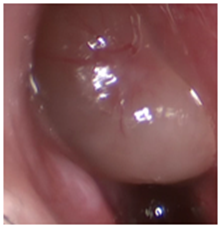

PCD is a rare, autosomal recessive disease with altered ciliary motility resulting in chronic upper and lower airway disease.3 Because of its low prevalence, there are few studies with significant numbers of cases, which makes it difficult to perform protocols and follow-up guidelines in these patients. A prevalence of 68% of nasal polyposis (Figure 1) is reported in these patients, 93% of rhinitis and 100% of signs of chronic rhinosinusitis (Figure 2).3 Functional endoscopic sinus surgery (FESS) is frequently indicated in cases of failure of medical treatment. It may be useful to decrease or eliminate upper and lower airway infections in these patients.4

Figure 1 Anterior rhinoscopy with nasal polyps.